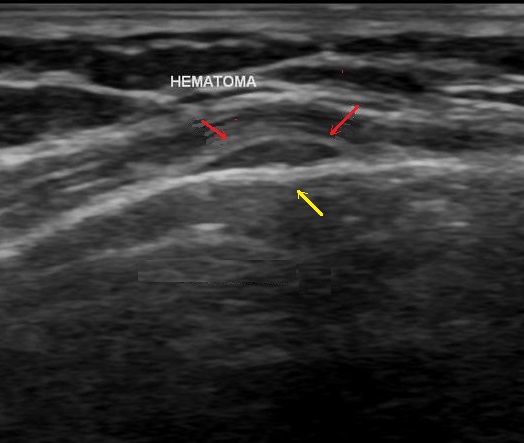

Image echographique une

fracture du côte du thorax avec aspect de

deplacement angulaire de côte affecte ( fleche jaune

) et image de hematome periostique hypo-echogene (

fleche rouge ) |